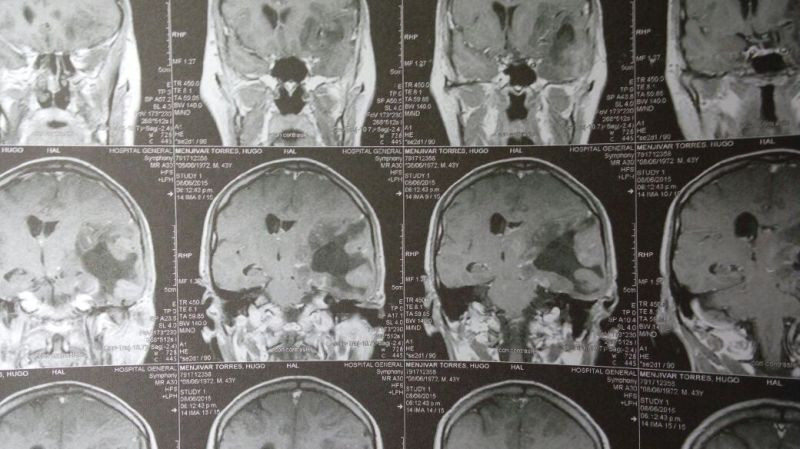

Oligodendroglioma temporal izquierdo Imagenes MRI Preoperatorio

Oligodendroglioma temporal Imagenes MRI Preoperatorio